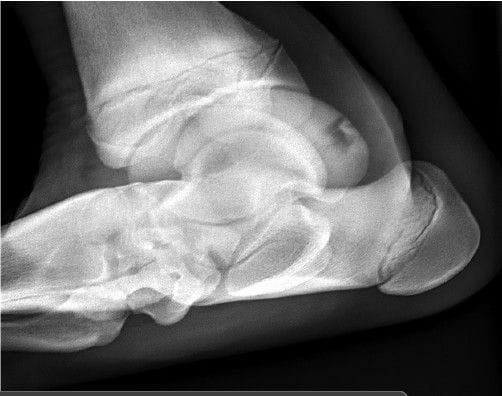

Flexed Pl30Pr45Lat-DoDiM oblique radiograph highlighting

the PMTR from a clinical case with a bone sequestrum. There is a

characteristic irregular, radiolucent, semilunar border separating the

fragment from the parent talus.